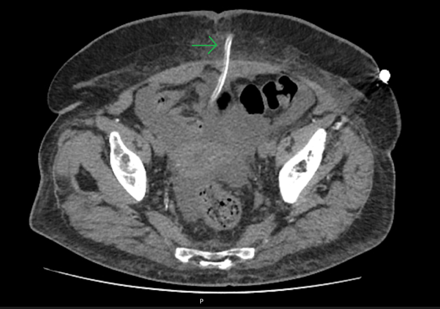

To assess for a possible peri-catheter leak and rule out a catheter fracture, a computed tomography (CT) scan was performed with contrast infusion into the peritoneal cavity (Figure 2 and Figure 3). The protocol included a standard non-contrast CT scan followed by a 2 h dwell of 1.36% glucose dialysate to which 100 ml of contrast was added, comprising a total of 2 liters of infused fluid.

Figure 3.

A second CT scan was performed afterward. Imaging showed dialysate drainage through the midline in the periumbilical region, where there was also significant adipose tissue densification. Intraperitoneal pressure was not measured at this time.